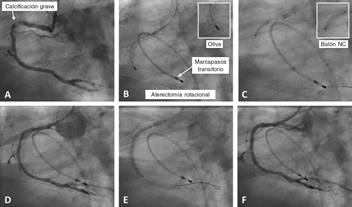

Figura 1. Caso de aterectomía rotacional sobre lesión calcificada en coronaria derecha. A: angiografía basal. B: rotablación de la lesión calcificada con oliva de 1,5 mm. C: predilatación con balón no distensible de 3 × 12 mm. D: resultado angiográfico tras la rotablación. E: implantación de stent farmacoactivo de 3 × 38 mm. F: resultado angiográfico final tras la posdilatación. NC: non-compliant balloon (balón no distensible).

La principal indicación de la AR es el tratamiento de LCGC no dilatables por métodos convencionales, mediante la modificación de placa, lo que facilita la adecuada expansión y la buena aposición del stent 10,11 (figura 1).